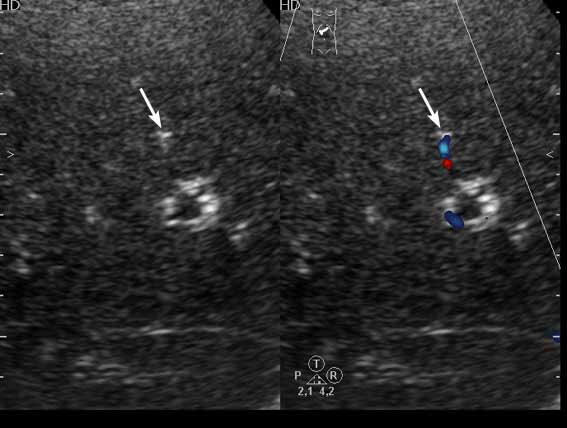

Получил данные за то, что, видимо, это мелкие конкременты в протоковой системе.

1) Эхогенные структуктуры дают твинклинг-артефакт (twinkling), характерный, например, для кальцийсодержащих образований.

2) Все пациенты, у которых наблюдалась подобная картина страдали ЖКБ, у всех был удален желчный пузырь.

Привожу еще один пример.

Женщина 70 лет,15 лет назад проведена холецистэктомия. Жалобы на боли в эпигастрии.